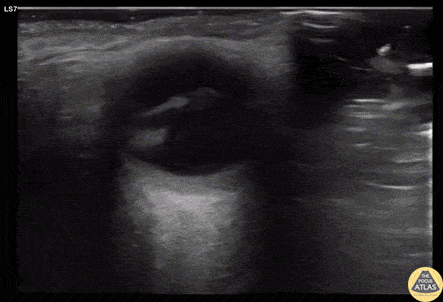

Orbital - Macula Off Retinal Detachment

70s F with PMH DM, HTN presented to the ED with 1 month of atraumatic, painless vision loss. Her visual acuity was limited to light perception only. POCUS was performed and is shown here. This clip of the eye is obtained with the left of the screen being medial/nasal, and the right of the screen being lateral/temporal. An irregular hyperechoic line is shown in the posterior chamber, which is attached to the optic disk, representing a detached retina. The patient’s presentation with profound painless vision loss, and detached lateral aspect of the retina is consistent with a macula off retinal detachment. Given the timeframe and POCUS findings, the patient was scheduled for urgent but nonemergent ophthalmology follow up for operative repair of the detached retina. Dr. Cody Brevik, PGY4 Denver Health Residency in Emergency Medicine